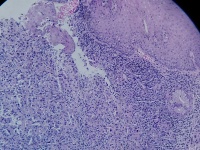

贲门活检

性别

男

年龄

68岁

上腹部不适,贲门可见不规则病灶,触之易出血

贲门粘膜

大体所见

腺癌